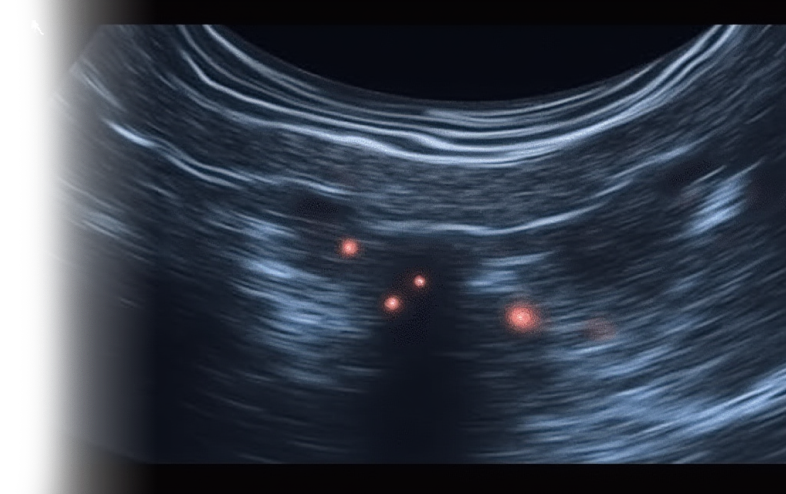

УЗИ лимфоузлов – важный метод исследования, позволяющий оценить различные заболевания щитовидной железы. При этом оценивается не только форма, структура, размер и контуры лимфоузлов, но и динамика противоопухолевой и противовоспалительной терапии.

Ультразвуковое исследование позволяет оценить как поверхностно расположенные лимфоузлы (шейные, подмышечные, паховые), так и глубоко расположенные (абдоминальные, тазовые).

Само исследование проводится с помощью ультразвукового аппарата, который передает звуковые волны через ткани и получает обратное отражение от органов.